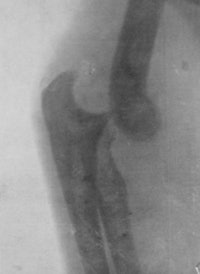

Early radiograph obtained at the Royal Free Hospital in London.

The Stobart Hospital had 100 beds, was located in an old concert hall, and was established before the "official" British Army hospitals had been set up. On 8 October 1914, they were under shellfire for 18 hours and their situation was desperate. They evacuated their patients, then started to walk to Holland and were picked up by three London buses and had to sit on ammunition cases. Stoney escaped from Antwerp only 20 minutes before the bridge was blown up. She continued work in France at the Chateau Tourlaville near Cherbourg. Radiography was used to show the positions of the fractures and the location of the shrapnel and bullet that could then be extracted.